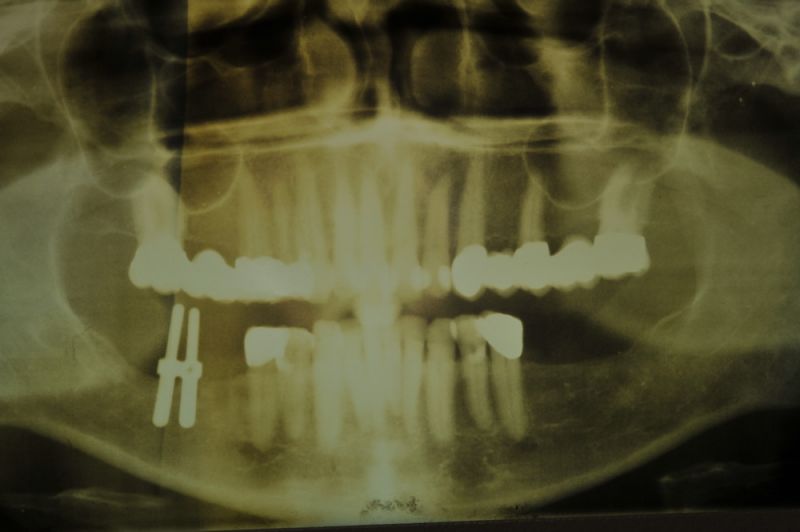

1. Notwendigkeit einer implantatgestützten Kronenversorgung mit der Vorgeschichte, dass die Patientin eine Vielzahl von Behandlern aufgesucht hatte, die eine Implantation im Unterkiefer als nicht durchführbar einschätzten.

2. Extrem schlechte knöcherne Verhältnisse im Unterkieferseitenzahnbereich, die sich intraoperativ noch einmal als ungünstiger darstellten, als bereits in den Voruntersuchungen erkennbar.

3. Sehr dünne Implantate, die von ursprünglich zwei je Kieferhälfte auf letztendlich drei je Kieferhälfte umgeplant werden mussten.